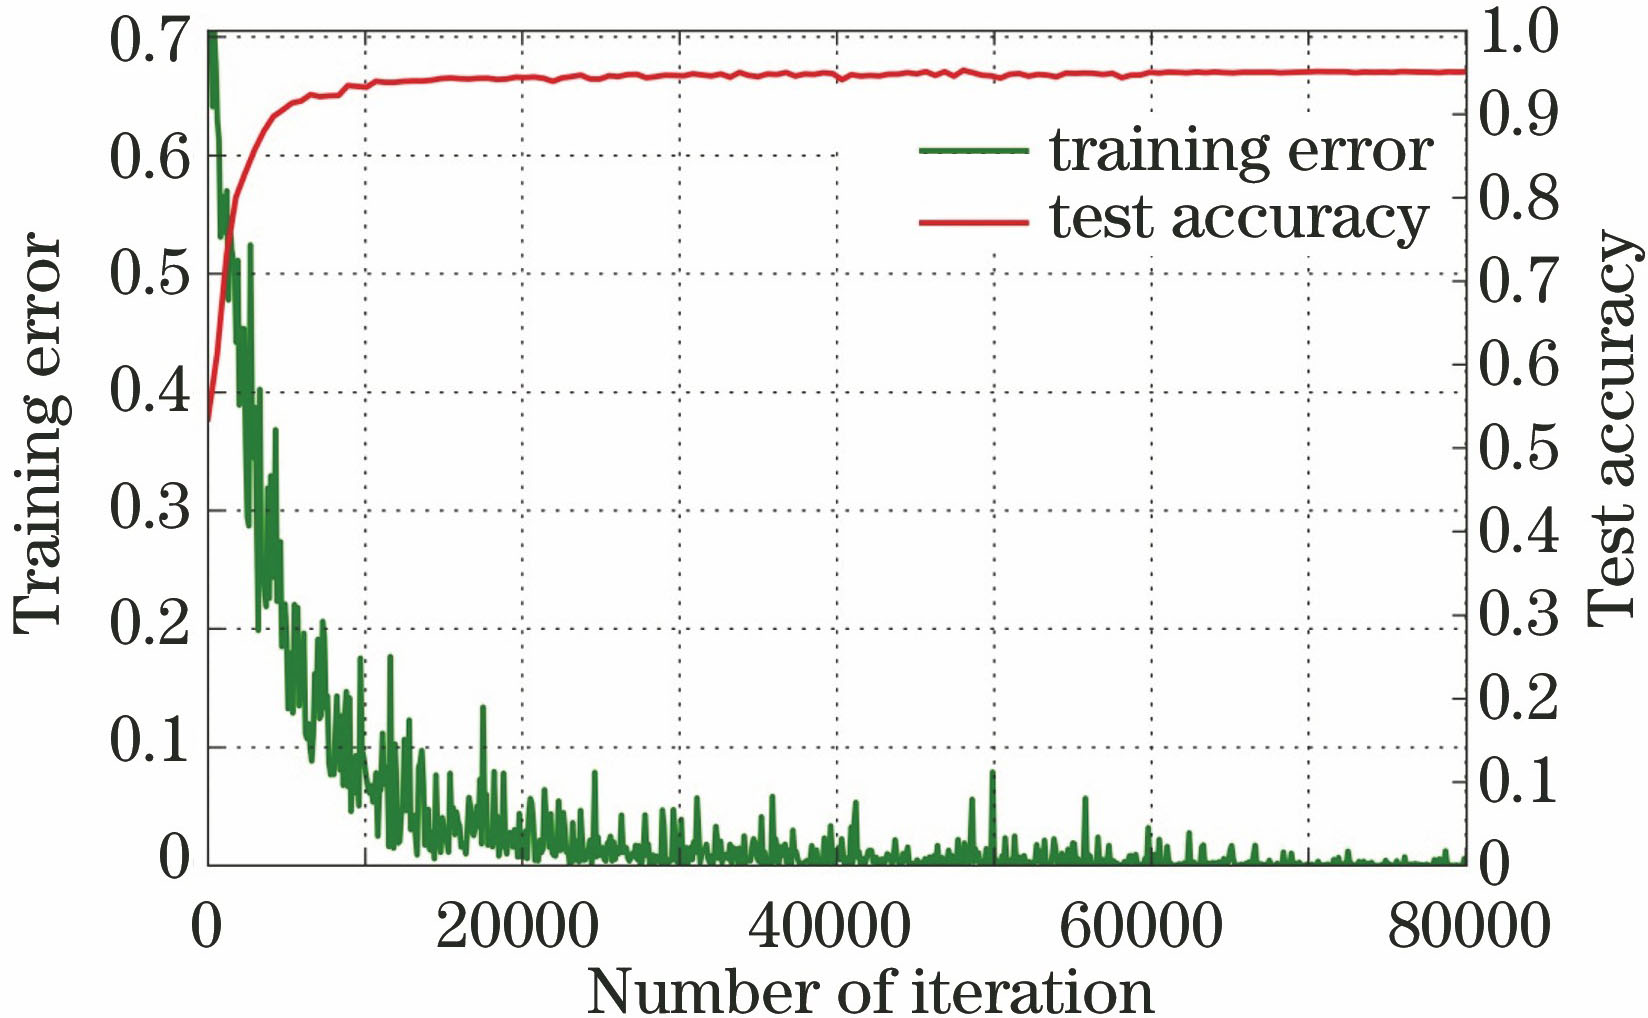

图 6. 3D卷积神经网络模型的训练误差和测试准确率曲线

Fig. 6. Training error and test accuracy curves of 3D convolution neural network model